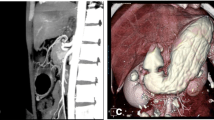

For each patient two models were reconstructed, i.e., the physiological (pre-surgical) stomach and the corresponding sleeved stomach at six months after surgery. The segmentation of the MRI scans led to the generation of 46 virtual solid stomach models (#23 pre-surgical stomachs + the corresponding #23 sleeved stomachs) by means of Synopsys Simpleware ScanIP. The specifics of the scanner machine and image resolution are reported in [22]. The volumetric identification was done from the MRI sequences of an empty stomach in the transverse plane, considering the optimal view for the recognition of gastroesophageal junction. The segmentation considered the whole stomach to the pyloric ring. The stomach volumes obtained were checked in the coronal plane and then exported. A double-layered geometry was generated from subsequent offsets of the external stomach surface, to obtain the submucosa-mucosa and muscularis layer (Fig. 1a) by means of Solidworks (Dassault Systemes, 2018). Different constant thicknesses were assigned to the submucosa-mucosa and muscularis layer, according to the considered gastric region, such as 0.9 and 1.2 mm in the fundus, 1.2 and 1.5 mm in the corpus, and 0.9 and 1.8 mm in the antrum, respectively [37, 39] (Fig. 1a).

The development of a patient-specific stomach model for finite element simulations. a From MRI the inner volume of the stomach is extracted; then the submucosa and the muscularis layer are created by means of surface offsets, with different thicknesses depending on the specific gastric region and layer. b Fine elements mesh of both the layers: six hexahedral elements modeled both the submucosa-mucosa layer and the muscularis stratum along the thickness direction

Finite element model and simulation

For the mechanical description of patient-specific stomach behavior, every double-layered stomach geometry was imported in the numerical solver Abaqus Explicit 2018 (Dassault Systemes Simulia Corp., Providence, RI) and then discretized in a fine mesh of linear hexahedral elements of 1-mm edge size (as reported in Fig. 1b), resulting in about 175,000 nodes for pre-surgical models and 75,000 nodes for sleeved models. To obtain a better description of the gastric wall elongation during these analyses, the thickness of the two layers was discretized with at least 5 internal nodes (3 elements for the submucosa-mucosa layer and 3 elements for the muscularis layer), as shown in the details of Fig. 1b. The mechanical behavior of the stomach tissues was defined by means of a fiber-reinforced hyperelastic constitutive formulation, which included the tissue anisotropy and nonlinear elasticity. The identification of human gastric parameters was performed by means of a coupled experimental and computational approach [39], where human resected stomachs were tested at tissue, sub-structural levels, and structural levels by tensile, membrane indentation, and inflation tests, respectively. From the tensile tests a set of preliminary constitutive parameters were extracted, then optimized and validated by comparing the other experimental results with computational outputs. Both the complete formulation and the procedure for parameters identification are fully reported in previous works [25, 35, 39]. The constitutive parameters adopted in this work for the two gastric layers belonging to the three stomach regions are shown in Table 2. Since during the LSG procedure the fundus is completely removed [40], when modeling sleeved stomachs, this region was omitted, and post-surgical models were described only by the corpus and the antrum, with related constitutive parameters.